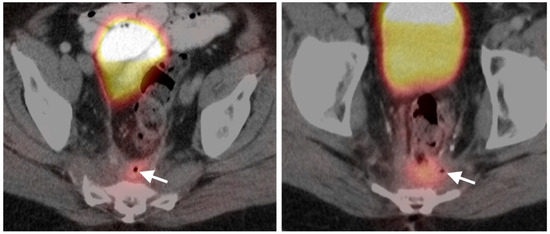

9. Bowel Adenocarcinoma: Colon, Rectum, Small Bowel

10. Anal Carcinoma